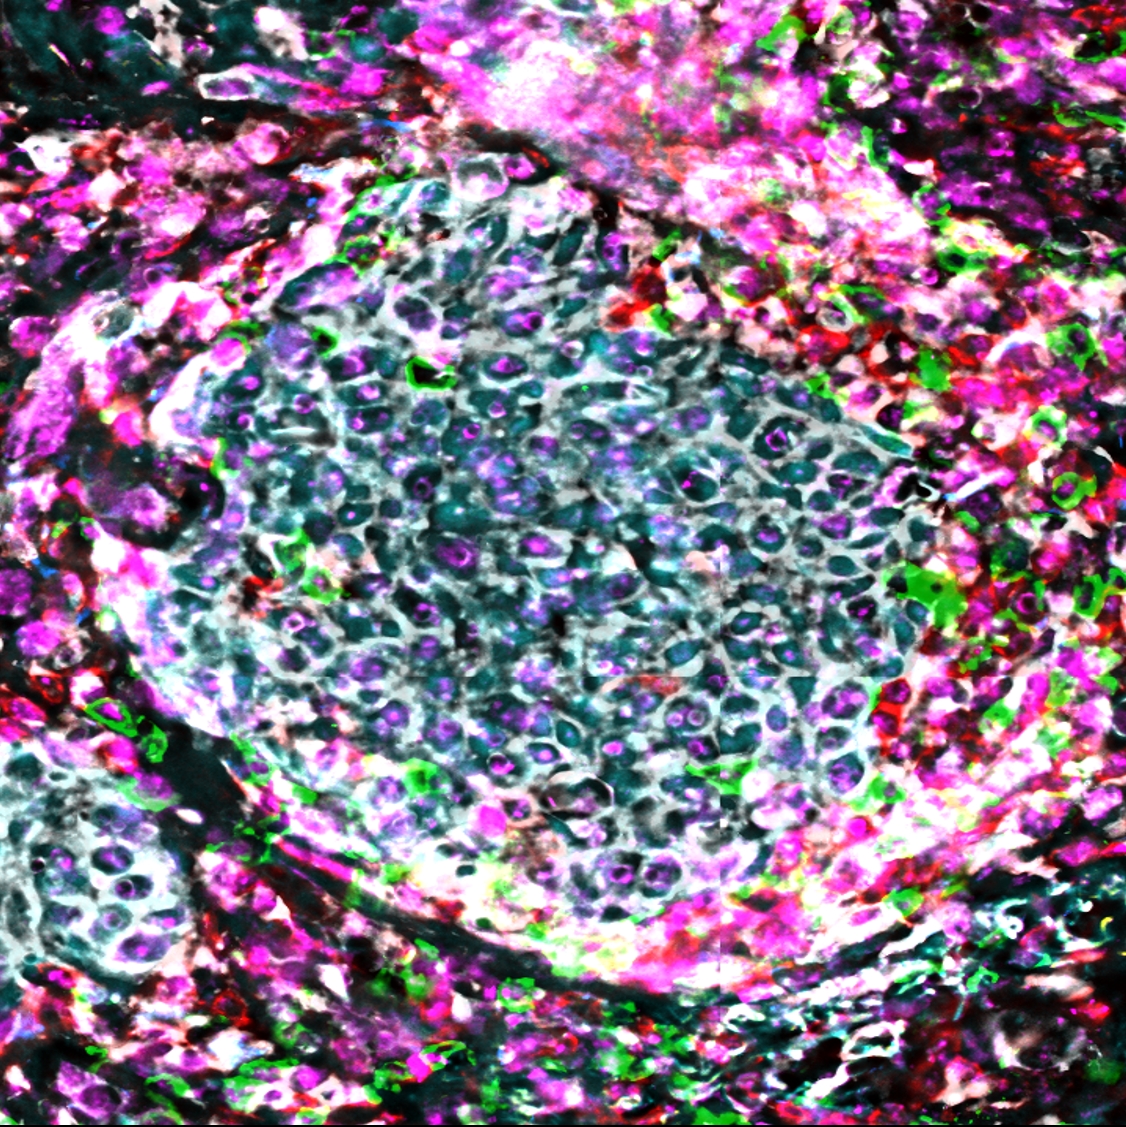

Geleitet wird die dahinterstehende klinische Forschungsgruppe KFO 337 von Prof. Dr. Dirk Schadendorf und Prof. Dr. Alexander Rösch. Im Fokus ihrer Teams stehen der besonders heimtückische Schwarze Hautkrebs sowie aggressive Tumore in Gehirn und Bauchspeicheldrüse. Die Forschenden haben herausgefunden, dass die untersuchten Tumorarten ähnliche Überlebensstrategien verfolgen. Krebsübergreifend konnten sie erste Mechanismen entschlüsseln, die dazu führen, dass Tumore widerstandsfähiger gegen traditionelle Behandlungsmethoden werden. Einige Tumorzellen sind demnach in der Lage, hoch dynamisch ihr Erscheinungsbild zu wechseln. Indem sie ihren sogenannten Zell-Phänotyp verändern, schützen sie sich gegen Angriffe durch das Immunsystem oder gegen einstmals effiziente Wirkstoffe.

Zudem sind manche Tumorzellen grundsätzlich therapieresistent und überleben von Anfang an Therapien und Angriffe von Immunzellen. Andere Tumorzellen wiederum entwickeln erst im Laufe der Zeit Resistenzen. „In einigen Fällen können wir die Resistenzen noch umgehen oder die Phänotypen gezielt ausschalten“, sagt Forschungskoordinator Prof. Dr. Alexander Rösch, Leitender Oberarzt an der Klinik und Poliklinik für Dermatologie, Allergologie und Venerologie des Universitätsklinikums Essen. „Wenn jedoch die Resistenzentwicklung zu weit fortgeschritten ist und sich genetisch fixierte Resistenzen zeigen oder Resistenzmechanismen zeitgleich auftreten, wird eine Umgehung der Resistenz immer schwieriger.“ Deshalb sollten therapie- und immunresistente Tumorzellen schon zu Beginn einer Therapie gezielt eliminiert werden.